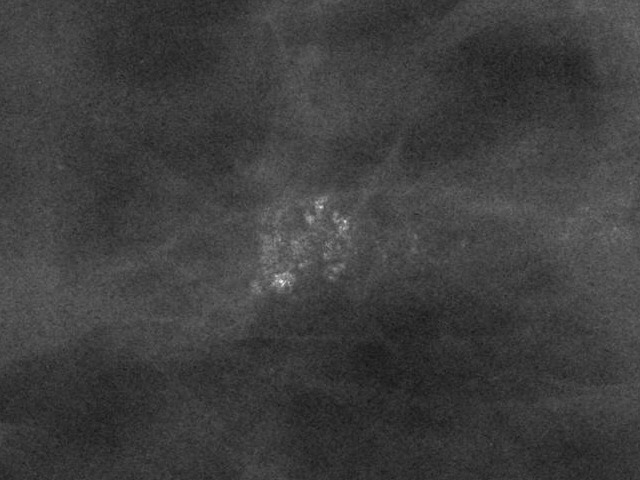

Bitte beurteilen Sie die Dignität bösartig gutartig